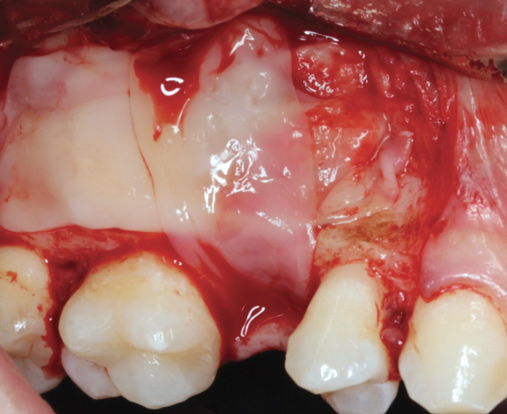

Fig 12. Lateral window sinus augmentation filled with a combination bone graft and PRF, to be covered by PRF membranes.

Figure 12

Fig 13. Lateral window closure with PRF membranes.

Figure 13

Because PRF also has been shown to be highly active on soft tissues, attempts have been made to use it as a sole barrier membrane to close lateral windows during sinus augmentation procedures (Figure 12 and Figure 13).28,29 Two studies to date from separate groups investigated the use of PRF in comparison with a collagen barrier membrane as a replacement material for lateral window closure. In both studies, PRF was shown to lead to similar results when compared with a collagen barrier membrane.28,29 These studies investigated implant stability and new bone formation around implants and/or implant success rates. Nevertheless, it remains difficult to evaluate whether PRF should be used as a complete barrier to soft-tissue invasion because of the estimated 10- to 14-day resorption period.

Therefore, lateral window closure is most frequently performed with a collagen barrier membrane. However, it is well-known that PRF is able to stimulate angiogenesis of tissues,30,31 and its use leads to faster soft-tissue regeneration. For these reasons, to further hasten soft-tissue healing and reduce patient morbidity PRF can be used over the top of collagen barrier membranes for improved tissue regeneration (Figure 14).